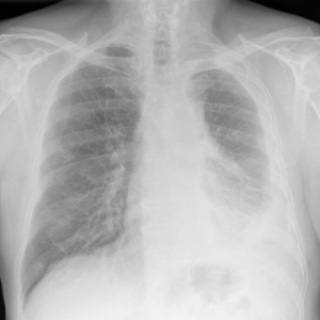

Digital chest x-ray of advanced malignant mesothelioma on left.

Lighter and hazy areas on the X-ray show possible mesothelioma tumors.

On a chest X-ray, pleural or pericardial mesothelioma tumors appear as wispy white areas around the lungs, while calcified tumors appear bright white. Bones appear white and healthy lungs are dark. Most abnormalities appear as lighter areas that are hazy or solid.

Tumors and scarring may distort chest anatomy. Compressed lungs or a raised diaphragm can be visible on an X-ray.

X-rays are 2D, making it hard to determine if a tumor is in the lung, pleura or the mediastinum around the heart. Additionally, X-rays don’t clearly show peritoneal or testicular mesothelioma. CT, MRI and PET/CT scans offer more detailed images for all mesothelioma types.